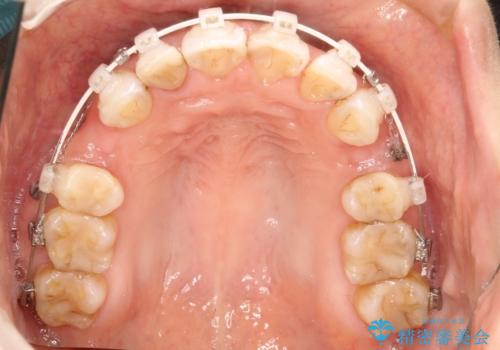

ワイヤーによる抜歯矯正でガタガタと深いかみ合わせの改善

- 上下の歯のがたつきを主訴に来院されました。

上下の前歯の叢生とかみ合わせが深い過蓋咬合という状態でした。

上下左右の歯を1本ずつ抜歯して、ワイヤーにて矯正を行いました。